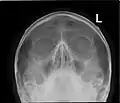

Paranasal sinuses

Paranasal sinuses seen in a frontal view